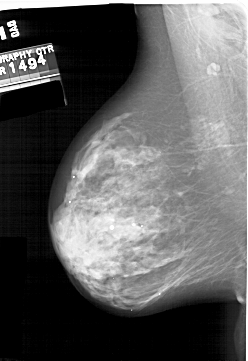

A_2000_1.RIGHT_MLO

RIGHT_MLO LINES 5896 PIXELS_PER_LINE 3961 BITS_PER_PIXEL 12 RESOLUTION 43.5 OVERLAY

FILE: A_2000_1.RIGHT_MLO.OVERLAY

TOTAL_ABNORMALITIES 1

ABNORMALITY 1

LESION_TYPE CALCIFICATION TYPE PLEOMORPHIC DISTRIBUTION SEGMENTAL

ASSESSMENT 4

SUBTLETY 4

PATHOLOGY MALIGNANT